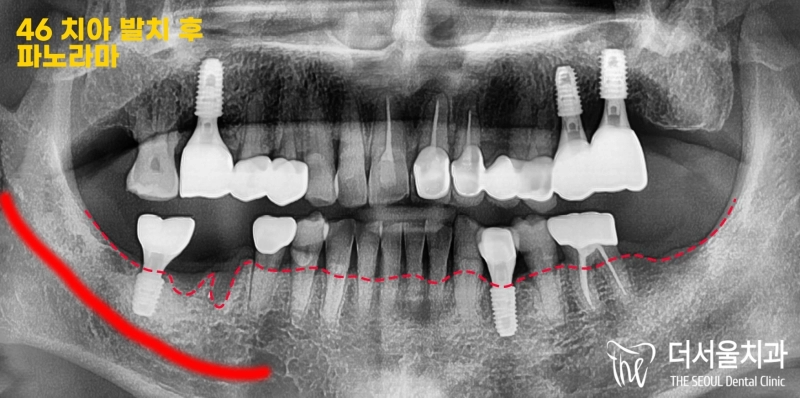

반갑습니다. 잠실 더서울 치과 박현성 원장입니다. 예전에 내원을 하셨던 환자 중에 따님분께 추천을 받아 오게 되었으며, 임플란트 수술을 받았던